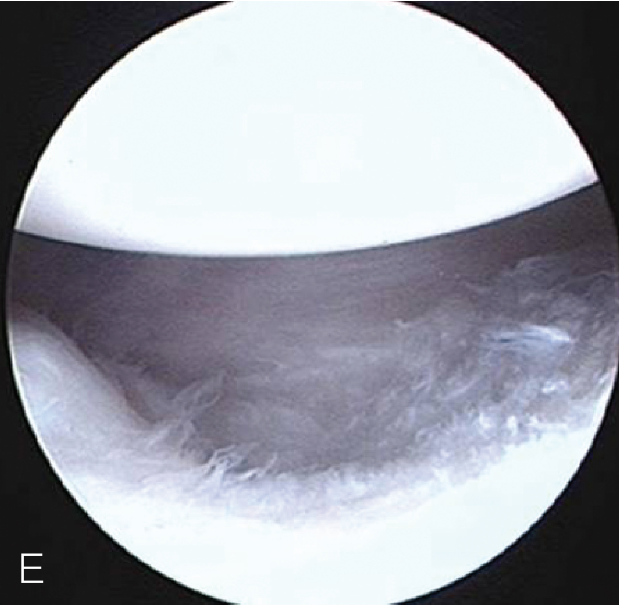

- 下一篇:「米粒」长在肩关节里,你见过吗?